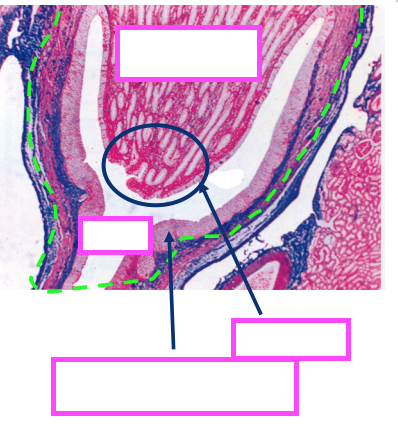

-Transitional epithelium is a stratified epithelium, capable of great extension, and characterized by the presence of urothelial cells (aka umbrella cells, transitional cells, dome cells) at the lumenal surface.

Urothelial Cells

Trigone

A triangular area of the bladder wall called the trigone, lies between the ureteral openings and is smoother than the rest of the wall. In females, this area is sometimes lined by stratified squamous epithelium rather than transitional epithelium. The trigone is supported against collapse, and allows complete emptying of the bladder.

Bladder Layers